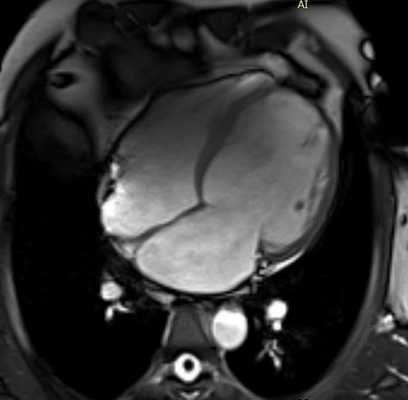

Подозрение на опухоли

Онкологические образования в сердце - редкое явление. Если на УЗИ есть сомнительные очаги, рекомендуется проверить пациента на МРТ. Это позволит достоверно сказать, какое новообразование, где расположено, его размеры, охарактеризовать границы патологического очага и состояние ближайших к нему здоровых тканей. Встречаются миксомы, фибромы, фиброэластомы, рабдомиомы. При злокачественных процессах можно заметить прорастание опухоли в соседние органы, лимфатические узлы, наличие метастазов.